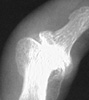

Radiographic Findings: Affected joint spaces are narrowed with reactive

subchondral sclerosis (eburnation). Other classic radiographic findings include

osteophytes and subchondral cysts. Heberden's nodes at the DIP joints and

Bouchard's nodes at the PIP joints of the hands are areas of osteophyte formation

and soft tissue swelling associated with osteoarthritis. Intraarticular loose

bodies can also sometimes be seen. Erosive osteoarthritis is an inflammatory

arthritis primarily seen in peri- and post-menopausal women; the distribution

pattern in the hands is the same as in primary osteoarthritis. However, this

process is associated with osteoporotic changes and erosions at the center

of the involved articular surfaces which create a "gull-wing" deformity.